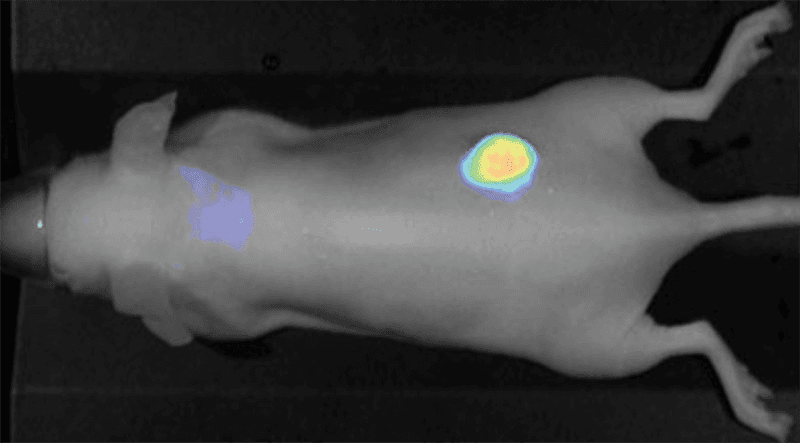

Examples of fluorescent probes developed against several receptor and transporter targets provide context on potential applications for other dye-labeled therapeutics. For instance, the GLUT1 glucose transporter can be targeted with a fluorescent-labeled IRDye® 2-deoxyglucose (2-DG) agent for longitudinal studies of tumor progression.3 EGF and integrin receptors can be targeted using IRDye EGF agent 4 or IRDye 800CW RGD,5, 6 respectively.

Figure 2. Nude mouse bearing subcutaneous tumors, U87 (left hip) and A431 (right hip), was imaged 24 h post intravenous injection of IRDye 800CW RGD (1 nmole). Image was captured on the Pearl Imager; 800 nm signal is presented in pseudo-color overlaid on a white light image of the mouse. Research conducted at LI-COR Biosciences.